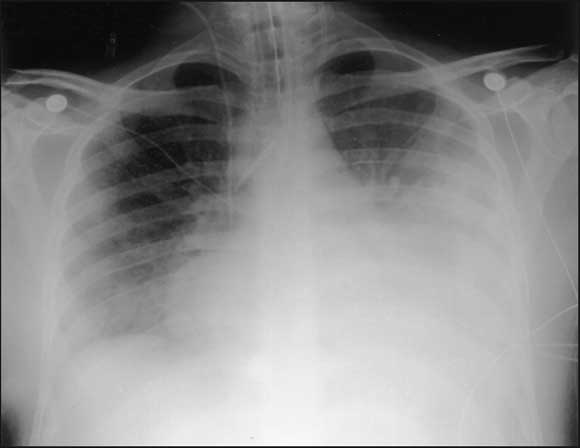

After an initial period of continuous positive airway pressure ventilation by mask, he was intubated and ventilated for respiratory exhaustion. Continuous veno-venous haemodiafiltration was commenced for oliguric renal failure (urea, 22.9 mmol/L [RR, 3–8 mmol/L]; creatinine, 498 μmol/L) in association with increasing acidosis (pH 7.37; base excess, − 6.1 mmol/L). Antibiotics were changed to benzylpenicillin (1.2 g four times a day), erythromycin (1 g four times a day), ceftazidime (1 g three times a day, to cover possible melioidosis) and metronidazole (500 mg twice daily). All cultures remained negative, and no serology results were available. The chest x-ray showed cardiomegaly, extensive consolidation in the left upper and lower lobes, and some right-sided patchy opacification ( Box).